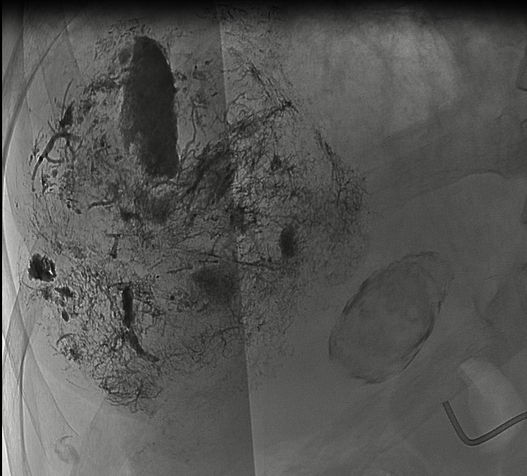

術(shù)中治療前造影